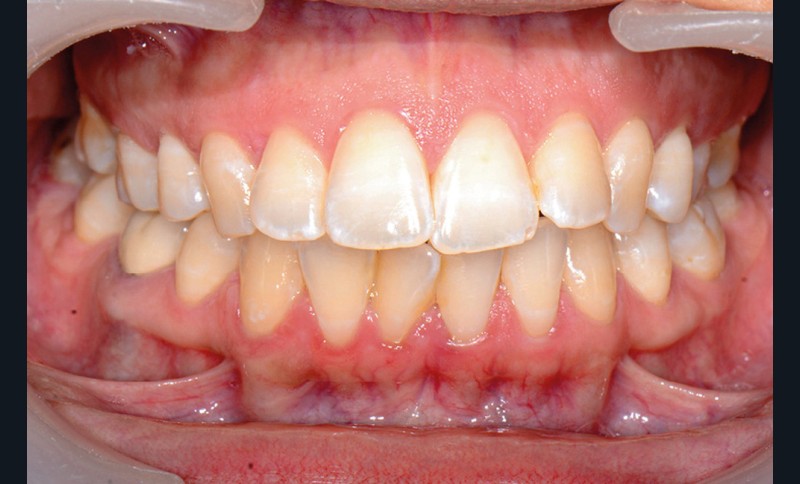

C’est précisément le cas de cette patiente de 33 ans qui présente une classe II squelettique par rétrognathie mandibulaire sur un schéma vertical hyperdivergent associée à une classe II/1 dentaire avec DDA par excès et biproalvéolie. Son profil est convexe, cis-frontal et, sur le plan fonctionnel, on peut observer une dysfonction linguale et une incompétence labiale au repos. Il en résulte une contracture des muscles de la sphère péri-orale lèvres jointes. La formule dentaire n’est pas complète puisque les quatre deuxièmes prémolaires ont été extraites lors d’un premier traitement orthodontique et qu’il y a également agénésie des troisièmes molaires 18 et 38 (fig 1 à 11).